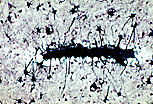

| 室管膜细胞(室管膜胶质细胞)衬于中枢神经系统内脑脊液循环的腔室表面:如本图所示的 脊髓 室管膜管,同时也衬于脑室壁。这类细胞为柱状,其顶端通过连接复合体相连,顶端有纤毛和少量微绒毛;基底端延伸出丝状胞质突起,难以观察到。 | |